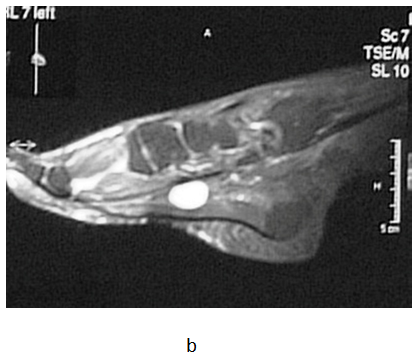

The operative and postoperative period passed without complications but she continued to have the same problems after the surgery. The patient received analgesic medications few months before she came to our Clinic. On her first visit at our outpatient clinic in July 2008, orthopedic shoes made on a plaster model of her feet with metatarsal pad were prescribed. On the control examination, the patient complained that the symptoms were worse and even disabling. An urgent MRI of the left foot was advised. The MRI showed a 2.5-centimeter in diameter, round, encapsulated mass that was differentially diagnosed as lipoma or neuroma (Figure 1a-1d). A surgical extirpation of the tumor was suggested. The operation was performed in September 2009 at the University Clinic for Orthopedic Surgery. At the level of the medial cuneiform bone of the foot, a round encapsulated mass, surrounding the medial communicant branch of medial plantar nerve was found (Figure 1e). Since the tumor could not be detached from the nerve, a neurectomy of the nerve proximal to the tumor was done. There were no complications in the operative and postoperative period. The excised tissue was sent for histological examination and the result confirmed it to be a Schwannoma (Figure 1f). After surgery, the patient was relieved of all symptoms. Follow-up visits were carried out at three, six and twelve months after the excision of the  Schwannoma. The patient had no pain and function of the left foot was normal at each consecutive control.

Figure 1 a, b) MRI cross section of the foot in T1 and T2 sequence (arrow shoving Schwannoma), c, d) MRI transverse section of the foot in T1 and T2 sequence e) macroscopic appearance of excised and cut in half Schwannoma f) Verocay body surrounded by Anthony B cells (HE, x100).